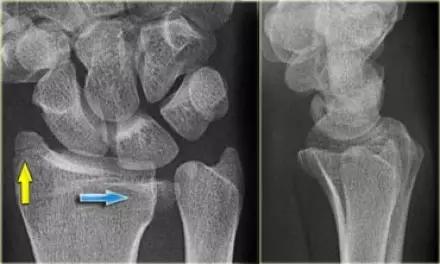

9. Essex-Lopresti 骨折

是桡骨头骨折伴有下尺桡关节脱位,导致骨间膜损伤,桡骨短缩。此种损伤,桡骨头骨折的诊断往往是明确的,容易忽视的是下尺桡关节脱位,特别是早期,下尺桡关节的症状不明显,X 线表示也不明显。

Essex-Lopresti 损伤。前后位(A)和侧位(B)示桡骨头关节内骨折(白色实线箭头);(C~E)伤后 1 个月复诊,患者诉腕关节疼痛,X 线(C,D)发现下尺桡关节脱位,(E)CT 进一步证实损伤的存在 (来源:Radiol Clin North Am. 2015 Jul;53(4):717-36)